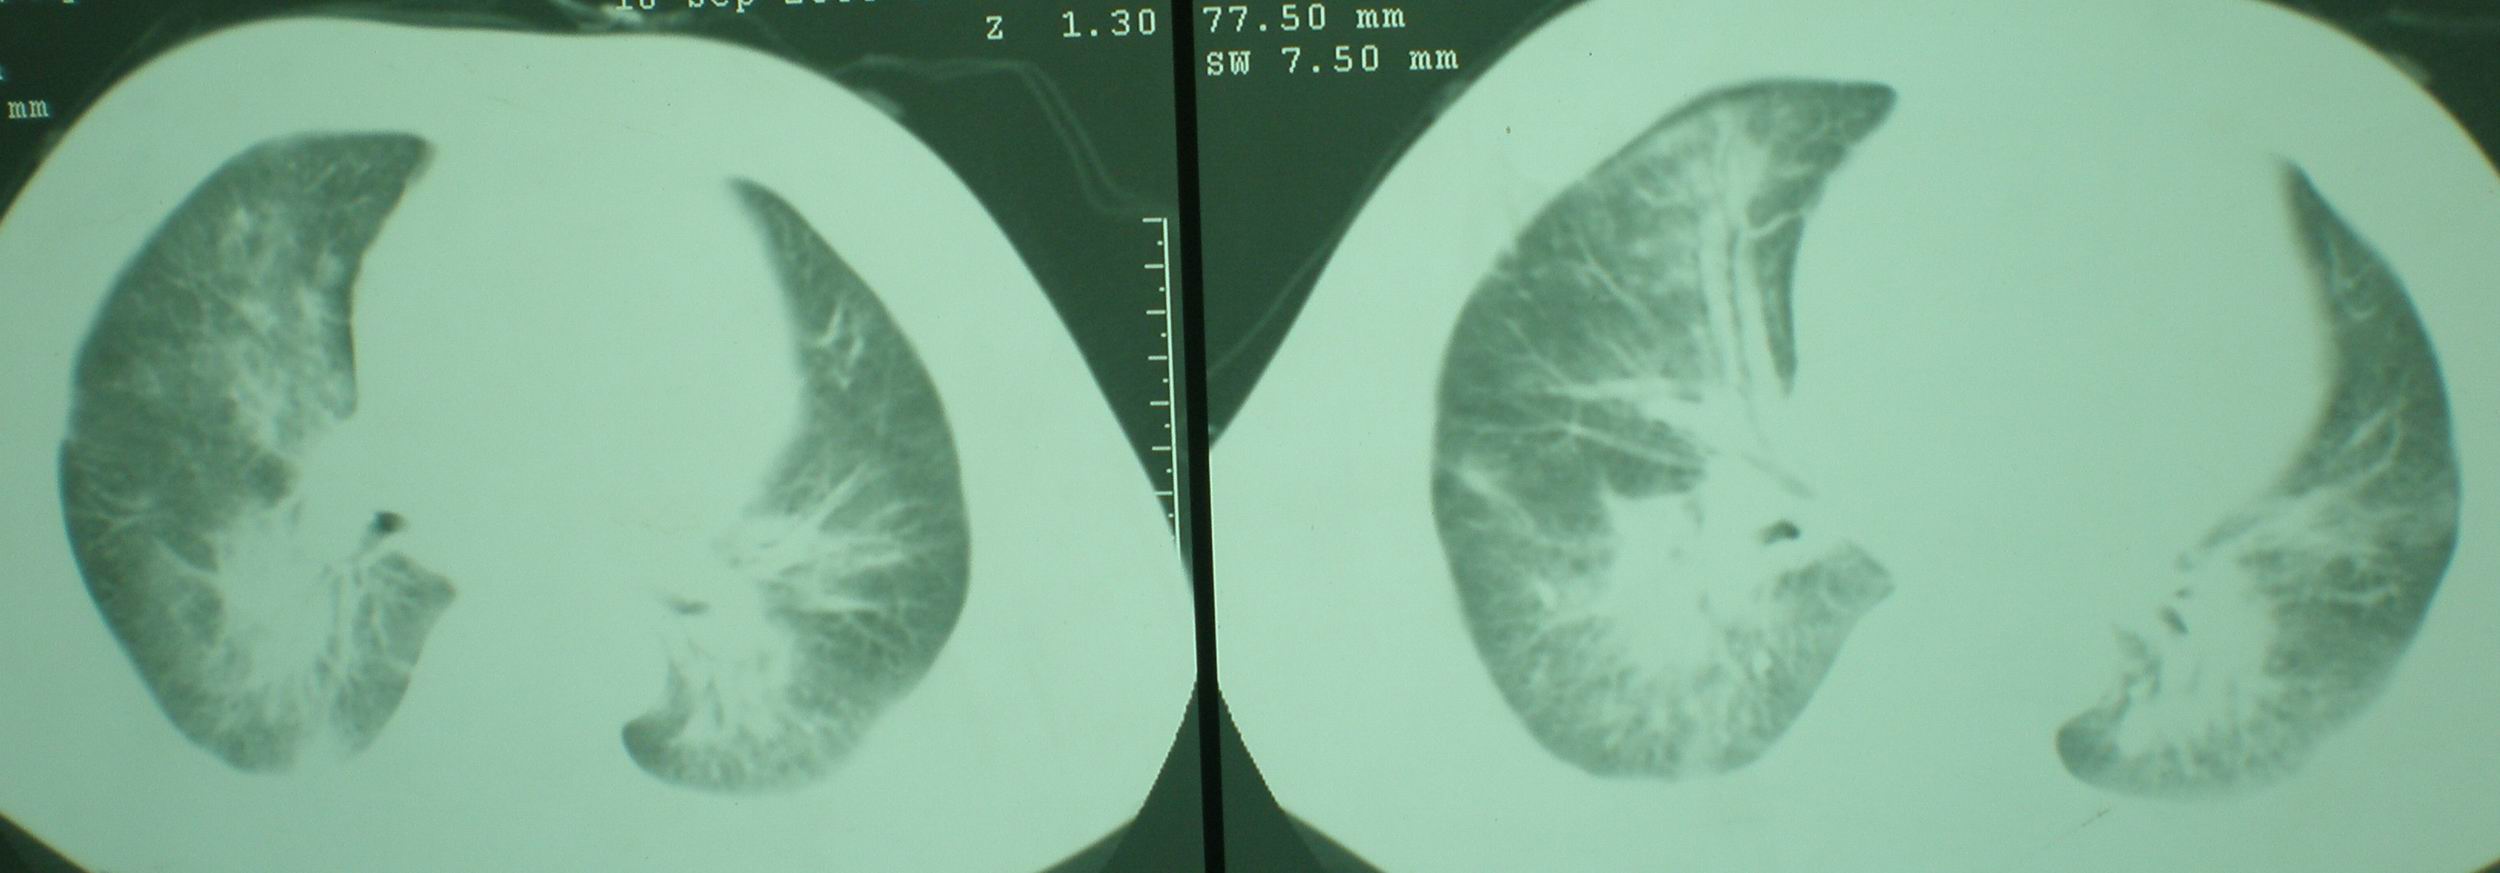

2008年11月18日今天的ct片

2008年9月18日ct片

2008年9月8日ct片:

我仔细看了下病人的出院小结,当时情况危急,诊断里有1型呼衰。心包周围的是脂肪密度。结合三次ct扫描的图象分析,个人认为:1、病人目前肺部病灶基本消失,双侧胸腔内少量积液,抗结核治疗才一个多月,就算是结核,抗结核治疗有效果,为何效果如此好,一点纤维灶的痕迹都没有呢,再就是患者做过气管镜检查及活检、痰检均未找到结核的证据。所以不支持结核的诊断。

2、结合现在的ct片,考虑:肺水肿及真菌感染,双侧胸腔积液。

急性呼吸窘迫综合征,肺水肿,与激素减量太快有关.双侧胸腔积液.

机遇性感染。双肺实质满布。且以肺门周围为主。不象结核。